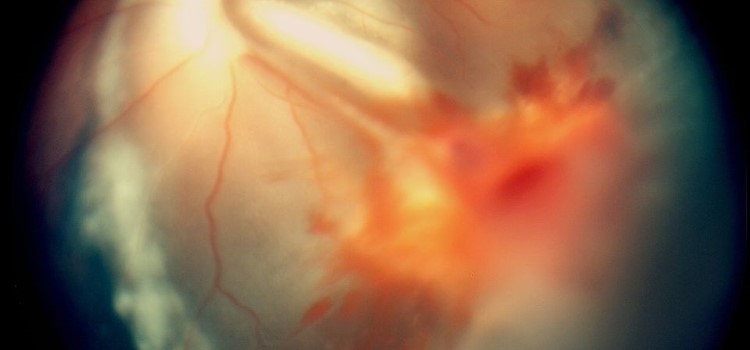

Hallan cómo se transmiten las imágenes de la retina al cerebro para ver en 3D 16.11.2020 El hallazgo ayudará a entender cómo se establece la lateralidad en otros circuitos neuronales, como el que permite la coordinación de los movimientos en los dos lados del cuerpo